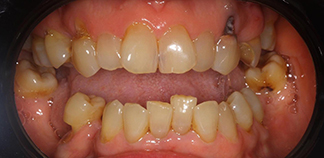

До лечения

Жалобы на отсутствие зубов.

Как лечили

Установлены шесть имплантов на верхней челюсти и четыре импланта на нижней. Зафиксированы постоянные коронки.

Лечащие врачи

МИРОШНИЧЕНКО Алексей Михайлович, БАЛЕВ Дмитрий Олегович